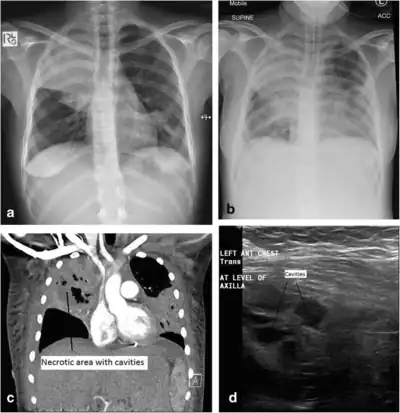

a) Initial plain chest radiograph showing a dense right upper zone airspace opacity and lingula airspace changes, consistent with multi-focal pneumonia. The following images were performed 24 h later. b) Plain chest radiograph with the patient intubated and ventilated revealing cavitation in the right mid to upper zones, pleural effusion and more general airspace changes bilaterally. c) Computed tomography (CT) scan, coronal view, demonstrating non-enhancing area (necrotic) thin-walled cavities within the right upper lobe and lingula. d) Lung ultrasonographic image displaying thin-walled cavities in the lingula region of the left lung. This requires further clarification.[note 1]